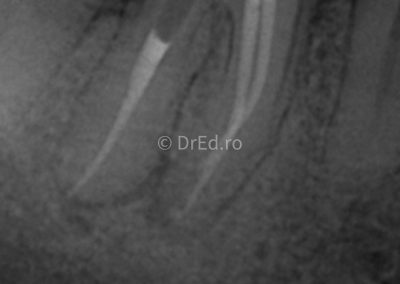

Galerie

Toate imaginile, fotografiile și radiografiile publicate pe acest site sunt protejate prin drepturi de autor și constituie proprietatea exclusivă a Dred.ro.

Aceste materiale sunt furnizate exclusiv în scop informativ și educațional și nu conțin date cu caracter personal sau informații care permit identificarea pacienților, în concordanță cu legislația privind protecția datelor cu caracter personal și GDPR.

Reproducerea, copierea, distribuirea, publicarea, transmiterea, modificarea sau orice altă utilizare, integrală ori parțială, a acestor materiale, în orice formă și prin orice mijloace, fără consimțământul prealabil scris al titularului drepturilor, este strict interzisă și poate atrage răspunderea civilă și/sau penală, în condițiile legii aplicabile privind drepturile de autor și protecția proprietății intelectuale.